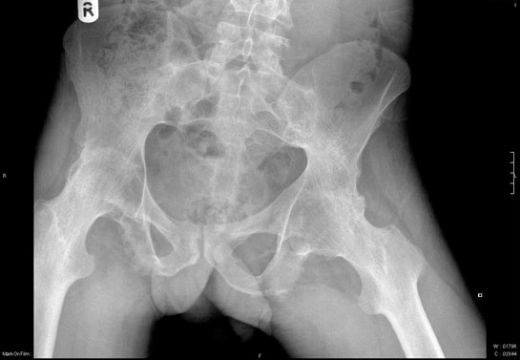

Kemik Ödeminin Tanısı Kemik ödeminin tanısı, genellikle fizik muayene ve görüntüleme yöntemleri ile konulur. Aşağıdaki yöntemler sıklıkla kullanılır: